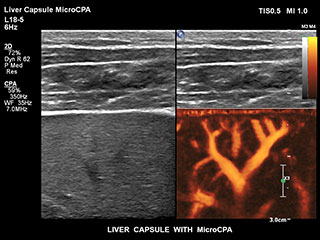

Ultrasound MicroCPA Small Vessel Visualization

MicroCPA

これまで、血流が少ない血管構造の血流情報は容易に収集できませんでした。しかし、EPIQの新しいMicroCPA機能を使用することで、低流速の微小循環を素早くかつ簡潔に描出できるようになり、臓器への灌流や小血管床の評価における診断確度が向上しました。